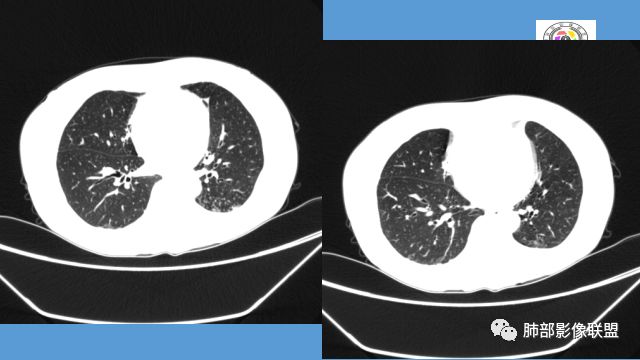

1.双肺多发病灶,结节影、树丫影,边缘分布……病灶符合继发性肺结核。

2.左肺上叶大片实变影,密度不均,体积轻度增大,注意轻到中度强化及血管影未见破坏、未见坏死空洞……病灶更符合炎症,而不大支持干酪性结核及肺鳞癌等,后两者的破坏能力是比较强的。

3.支气管阻塞,沿途可见钙化及液性潴留……更符合支气管内膜结核。

综上,双肺继发性肺结核诊断应当成立;左肺上叶大片影,以支气管内膜结核伴阻塞性炎症解释更为合理。